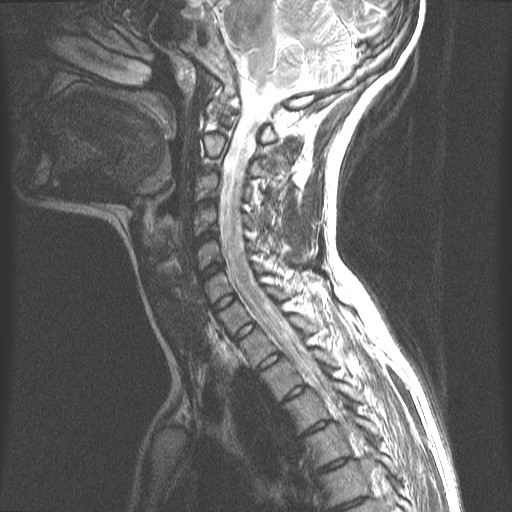

Centrale Wervel Zuil